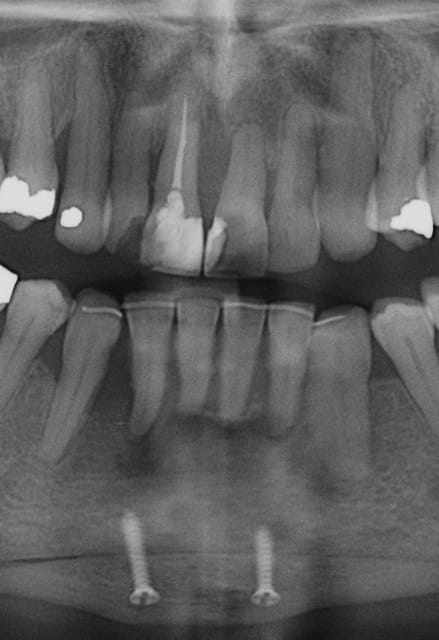

Patiente 58 ans à eu une chirurgie à visée esthétique et "fonctionnelle" adressée pour détartrage en urgence...je ne suis pas spécialiste mais je trouve que la greffe mentonnière est très bof

lésion apicale sur 42 risque de contamination sur la vis en regard..

j'ai demandé un scan en urgence.

Nous sommes d'accord pour la chirurgie mais secteur 4 il y a 2mm être là plastie et la mdble, ça ne me fais pas rêver

La chirurgie à 6 mois

La lésion sur 42 était sans doute déjà là le jour de la chir... c'est plus ça qui craint effectivement.

42 nécrosée?

Nous sommes d'accord pour la genioplastie je me suis mal exprimé ce qui m'inquiète c'est la proximité de la greffe, pardon genioplastie et de l'infection de 42, d'une part et la mauvaise liaison de la genioplastie secteur 4, mais je suis peut-être pessimiste.

Plusieurs points: les vis de 15mm x 2mm qui transfixent c'est pas top, une seule plaque, qui plus est non réglable de chaque côté, c'est encore moins top. C'est une plaque de fracture.

En mandibulaire gauche c'est quoi ce fil d'osteosynthese? Un troisième fragment? En laissant l'apex de la 48 pile sur le trait d'osteotomie, je dis chapeau.

Pour la lésion de 42, ca peut être lié à la genio. Forage hasardeux? Mais je vote plus pour une lésion endo/paro

il y a de l'os autour de 11 et 21 ?